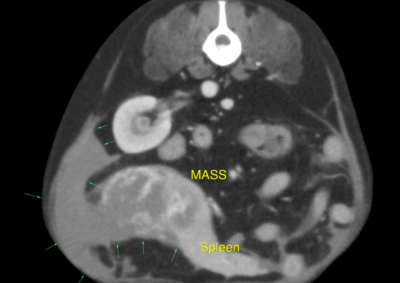

腫瘍外科 注意 ボタンをクリックした先に、治療中および手術中の画像が説明で使用されている場合がございます。 そのような画像に弱い方は閲覧なさらないようお願いいたします。 軟部組織外科腫瘍外科 肺葉切除術 腫瘍外科 胃の腫瘍 軟部組織外科腫瘍外科 大腸腺癌 腫瘍外科 肺葉切除術 腫瘍外科 肝葉切除術 腫瘍外科救急・集中治療 脾臓腫瘤破裂による腹腔内出血 腫瘍外科脳神経科 鼓室に発生した扁平上皮癌 軟部組織外科腫瘍外科救急・集… 脾臓破裂 軟部組織外科腫瘍外科救急・集… 出血性心タンポナーデに対する胸腔鏡下心膜切除術 腫瘍外科 前立腺癌を外科的に切除した犬の1例 腫瘍外科 Mott細胞分化を伴う腸管リンパ腫 Intestinal lymphoma with ... 腫瘍外科 肝細胞癌のチワワの1例 <1234567> 症例カテゴリー 放射線治療整形外科軟部組織外科脳神経外科内科腫瘍外科救急・集中治療リハビリテーション科腫瘍内科内視鏡科脳神経科呼吸器外科中医・漢方猫の腎移植循環器科